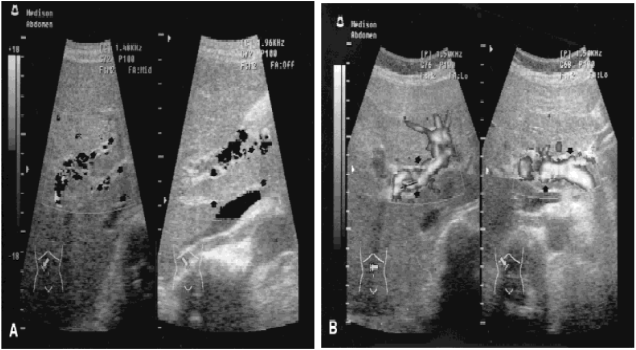

Поскольку ТВВ не имеет специфических признаков, следует использовать визуализирующие методы исследования, направленные на поиск тромботического очага. Такие исследования включают: доплеровское исследование, КТ, МРТ, ангиографию. Цветное доплеровское исследование (ЦДИ) необходимо провести в первую очередь, так как это наиболее дешевый, эффективный и неинвазивный метод. Однако чувствительность и специфичность ЦДИ довольно низки, к тому же различаются у разных больных. Только у пациентов с обширными тромботическими поражениями и полным закрытием просвета сосудов ЦДИ будет иметь высокую чувствительность и специфичность. Пропуск патологии при ЦДИ возможен, но в том случае, если сохраняется остаточный кровоток по воротной вене. В крупном клиническом исследовании, проведенном в г. Бирмингеме (Великобритания), было показано, что чувствительность и специфичность ЦДИ достигают 73% и 99% соответственно. В другой публикации сообщалось, что использование внутривенного контрастирования увеличивает точность ЦДИ. Пример доплеровского исследования при ТВВ приведен на Рисунке 1.

Рисунок 1. (A) Доплеровская сонограмма показывает компактный тромб в воротной вене (стрелки) без доплеровского сигнала. (В) Тот же больной через 3 месяца. Тромб в воротной вене почти полностью лизировался, хорошо виден ток крови через затромбированный ранее участок (стрелки).